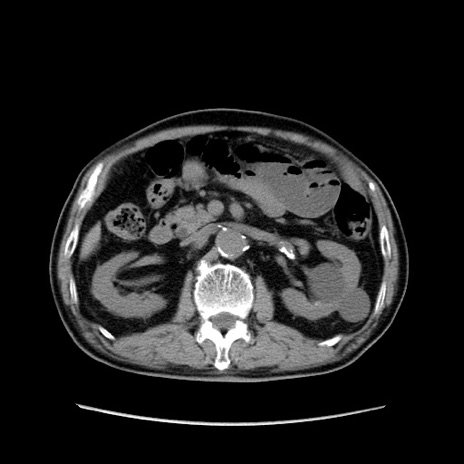

症例24(横断像)

【症例】80歳代男性

【主訴】左側腹部痛、嘔吐

【現病歴】本日早朝より左腹部に痛みあり。昼頃嘔吐認めたため、救急要請。

【既往歴】直腸癌(Mile手術)、胆摘

【身体所見】意識清明、BT 35.9℃、BP 221/93mmHg、SpO2 97%(RA) 、腹部:左ストーマ周囲に限局性の腹部膨隆あり。 膨隆部自発痛・圧痛あり・軟。

【データ】WBC 7700、CRP 0.09